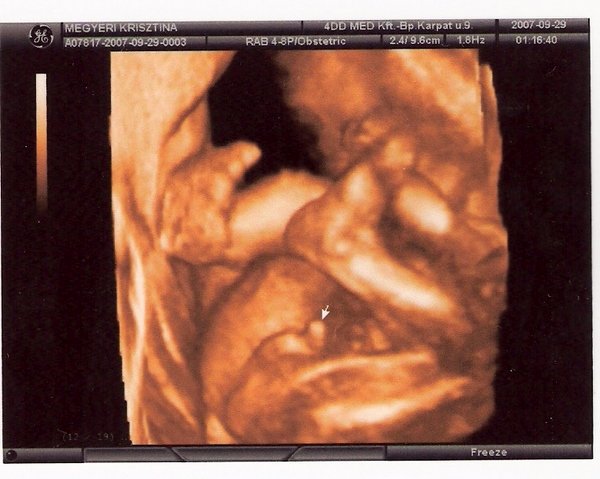

Pil, gratula Kispetihez!!! Nagyon kis édes, és ez a kukacos kép. Nosztalgiázok.